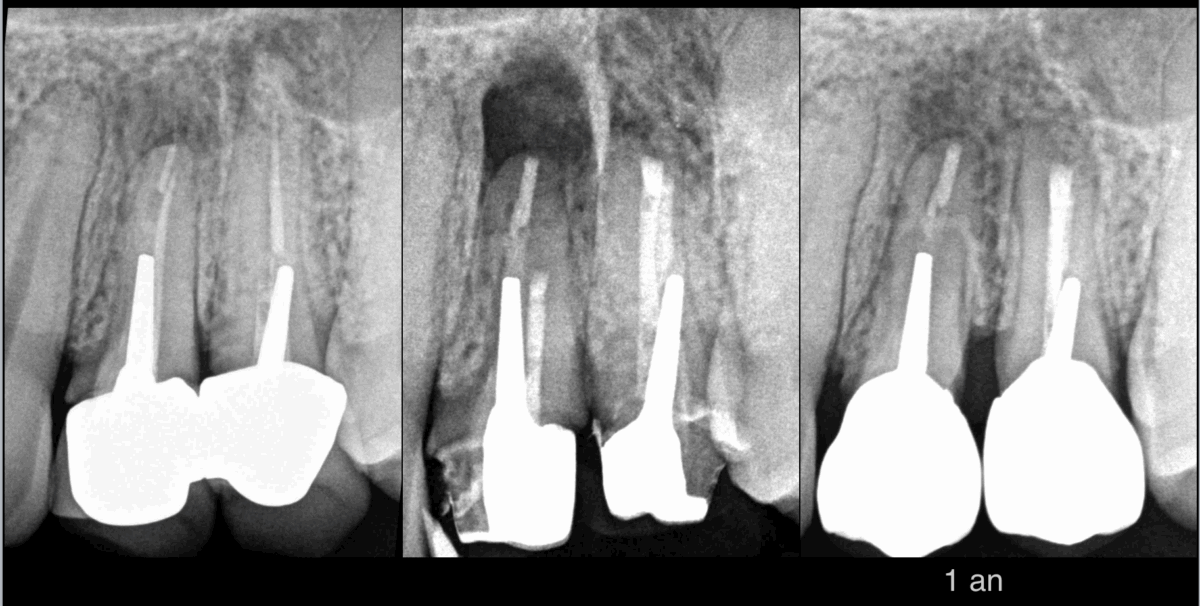

🦷 Dents 23 24

🔄 Pulpes précédemment traitées

⚠️ Parodontites apicales symptomatiques

💡 𝐑𝐞́𝐟𝐞𝐜𝐭𝐢𝐨𝐧 𝐩𝐫𝐨𝐭𝐡𝐞́𝐭𝐢𝐪𝐮𝐞 indiquée → retraitement canalaire.

🛠️ Dépose réalisée par notre cher correspondant.

➡️ Nous nous rendons compte :

• que 𝐥𝐚 𝐝𝐞́𝐩𝐨𝐬𝐞 𝐝𝐞𝐬 𝐢𝐧𝐥𝐚𝐲-𝐜𝐨𝐫𝐞 𝐜𝐨𝐦𝐩𝐫𝐨𝐦𝐞𝐭𝐭𝐫𝐚 les pronostics biomécanique et prothétique

• que 𝐥𝐞𝐬 𝐢𝐧𝐥𝐚𝐲-𝐜𝐨𝐫𝐞 𝐞𝐧 𝐥’𝐞́𝐭𝐚𝐭 sont exploitables pour la réalisation de nouvelles prothèses

✅ 𝐈𝐧𝐥𝐚𝐲-𝐜𝐨𝐫𝐞 sont laissés en place.

🤝 𝐃𝐞́𝐜𝐢𝐬𝐢𝐨𝐧 𝐭𝐡𝐞́𝐫𝐚𝐩𝐞𝐮𝐭𝐢𝐪𝐮𝐞 modifiée en accord avec le patient :

🔬 𝐌𝐢𝐜𝐫𝐨𝐜𝐡𝐢𝐫𝐮𝐫𝐠𝐢𝐞 𝐞𝐧𝐝𝐨𝐝𝐨𝐧𝐭𝐢𝐪𝐮𝐞 des canaux V et P de 24 25.